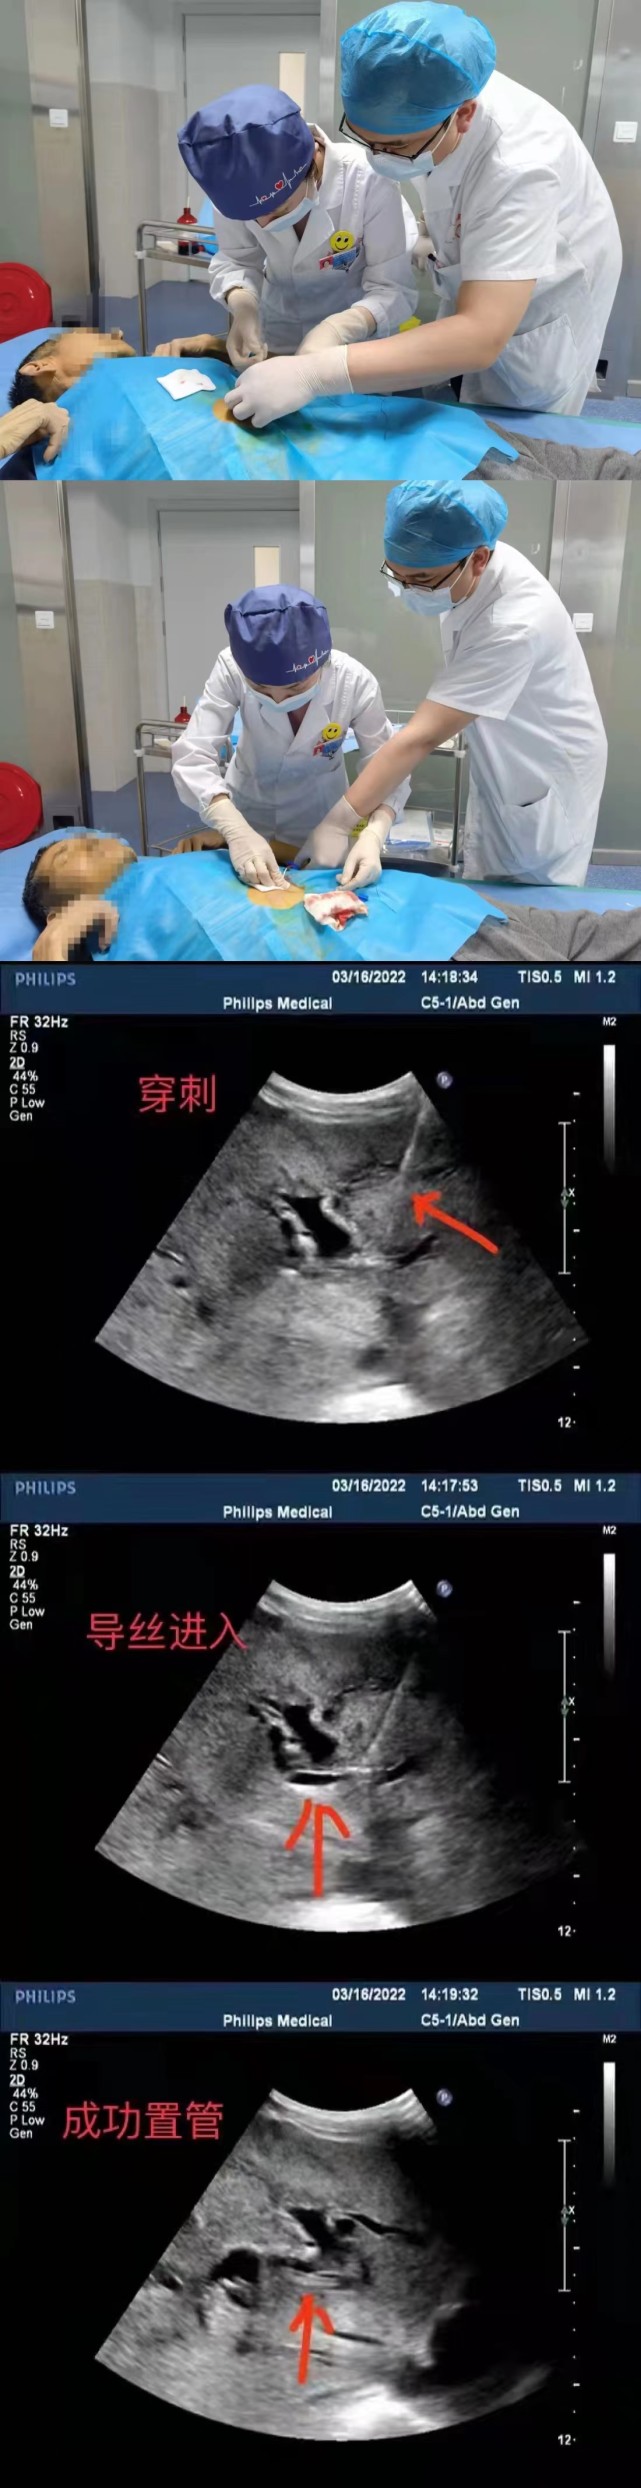

湘西州民族中医院成功完成该院首例超声引导下经皮肝胆管穿刺置管引流

图片尺寸641x2488

华亭市人民医院超声科自主完成首例超声引导下ptcd

图片尺寸3264x2448